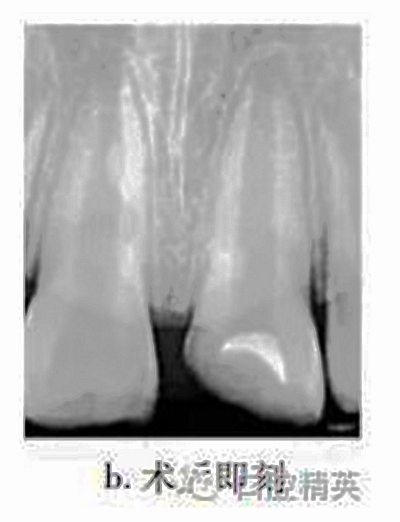

治療:局麻下調(diào)牙合,21揭髓頂,去除可能污染的冠部牙髓,達(dá)根管口處,呈整齊斷面,生理鹽水反復(fù)沖洗以去盡組織碎屑,并用蘸有少許生理鹽水的小棉球置于牙髓斷面壓迫止血,將MTA按操作說明要求和生理鹽水按3∶1比例調(diào)和均勻呈糊狀,直接覆蓋在牙髓斷面約1mm,玻璃離子水門汀暫封(圖b)。